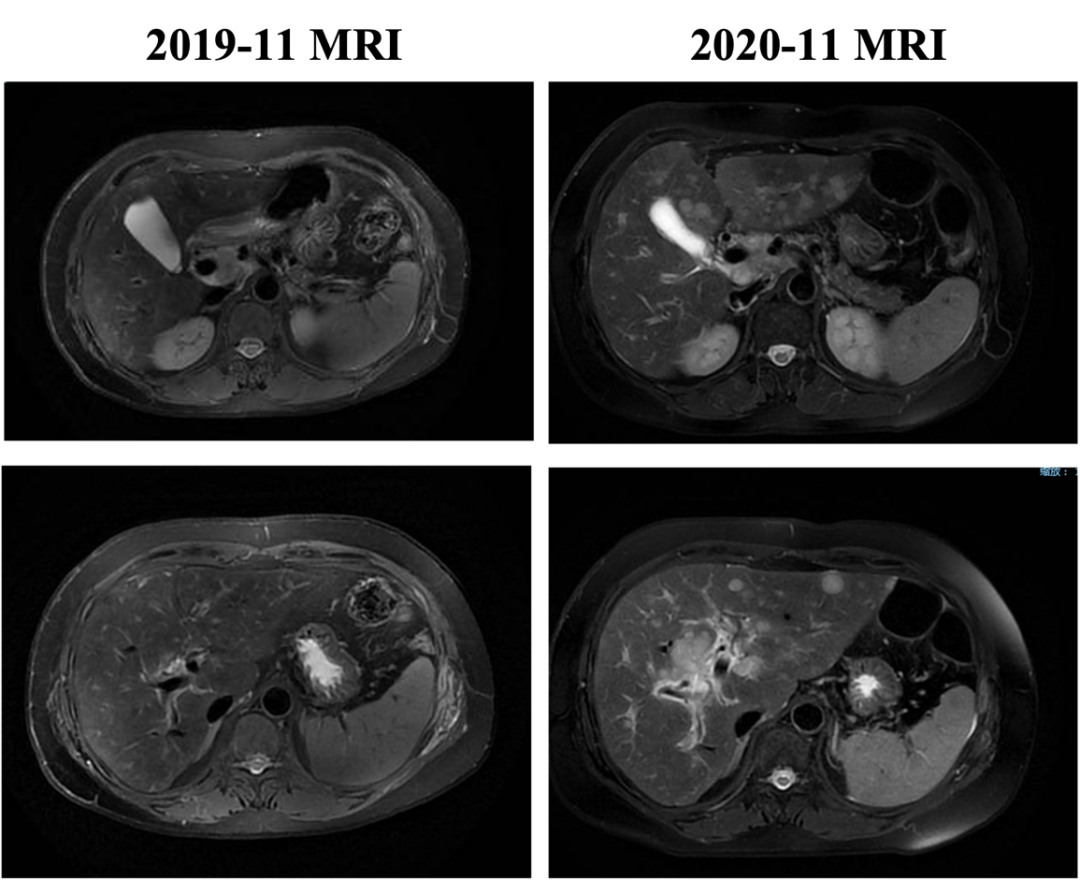

自2020-11-10行白蛋白紫杉醇+伊尼妥单抗治疗2周期,具体:伊尼妥单抗8mg/kg 首剂,6mg/kg 后续d1+白蛋白紫杉醇125mg/m2 200mg d1、d8,Q21d。2周期后肝转移增多、增大,肝门区及门腔间隙肿大淋巴结部分缩小,综合评效PD,PFS为1.5月。

图6. 五线治疗